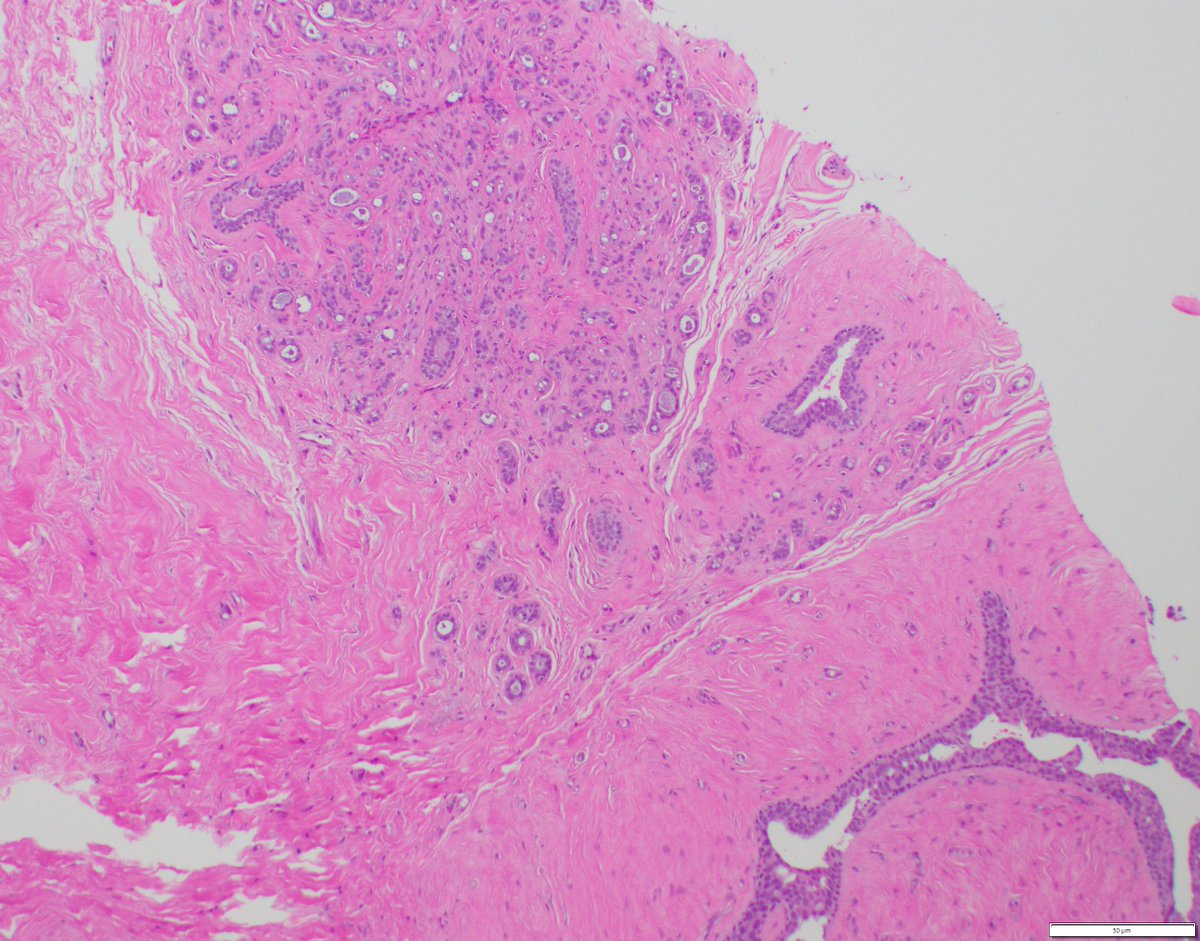

Ductal carcinoma in situ (DCIS) with lobular cancerization and pagetoid growth pattern, E-cadherin exhibits intact membranous expression. #breastpath #pathresidents #pathtwitter #BreastPatholog1 Columbia Pathology Columbia Pathology Residency

Ductal carcinoma in situ (DCIS) with lobular cancerization and pagetoid growth pattern, E-cadherin   exhibits intact membranous expression.

#breastpath #pathresidents #pathtwitter #BreastPatholog1